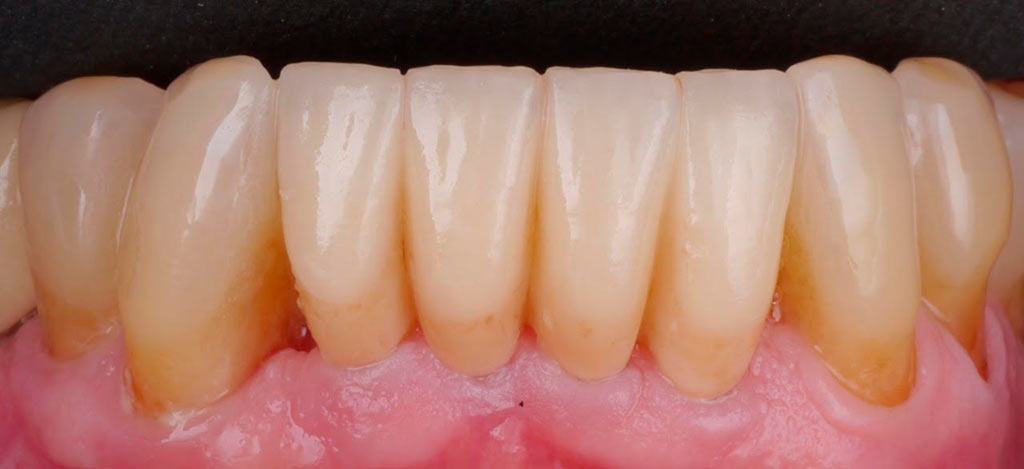

Rehabilitacion de paciente con destrucción dental